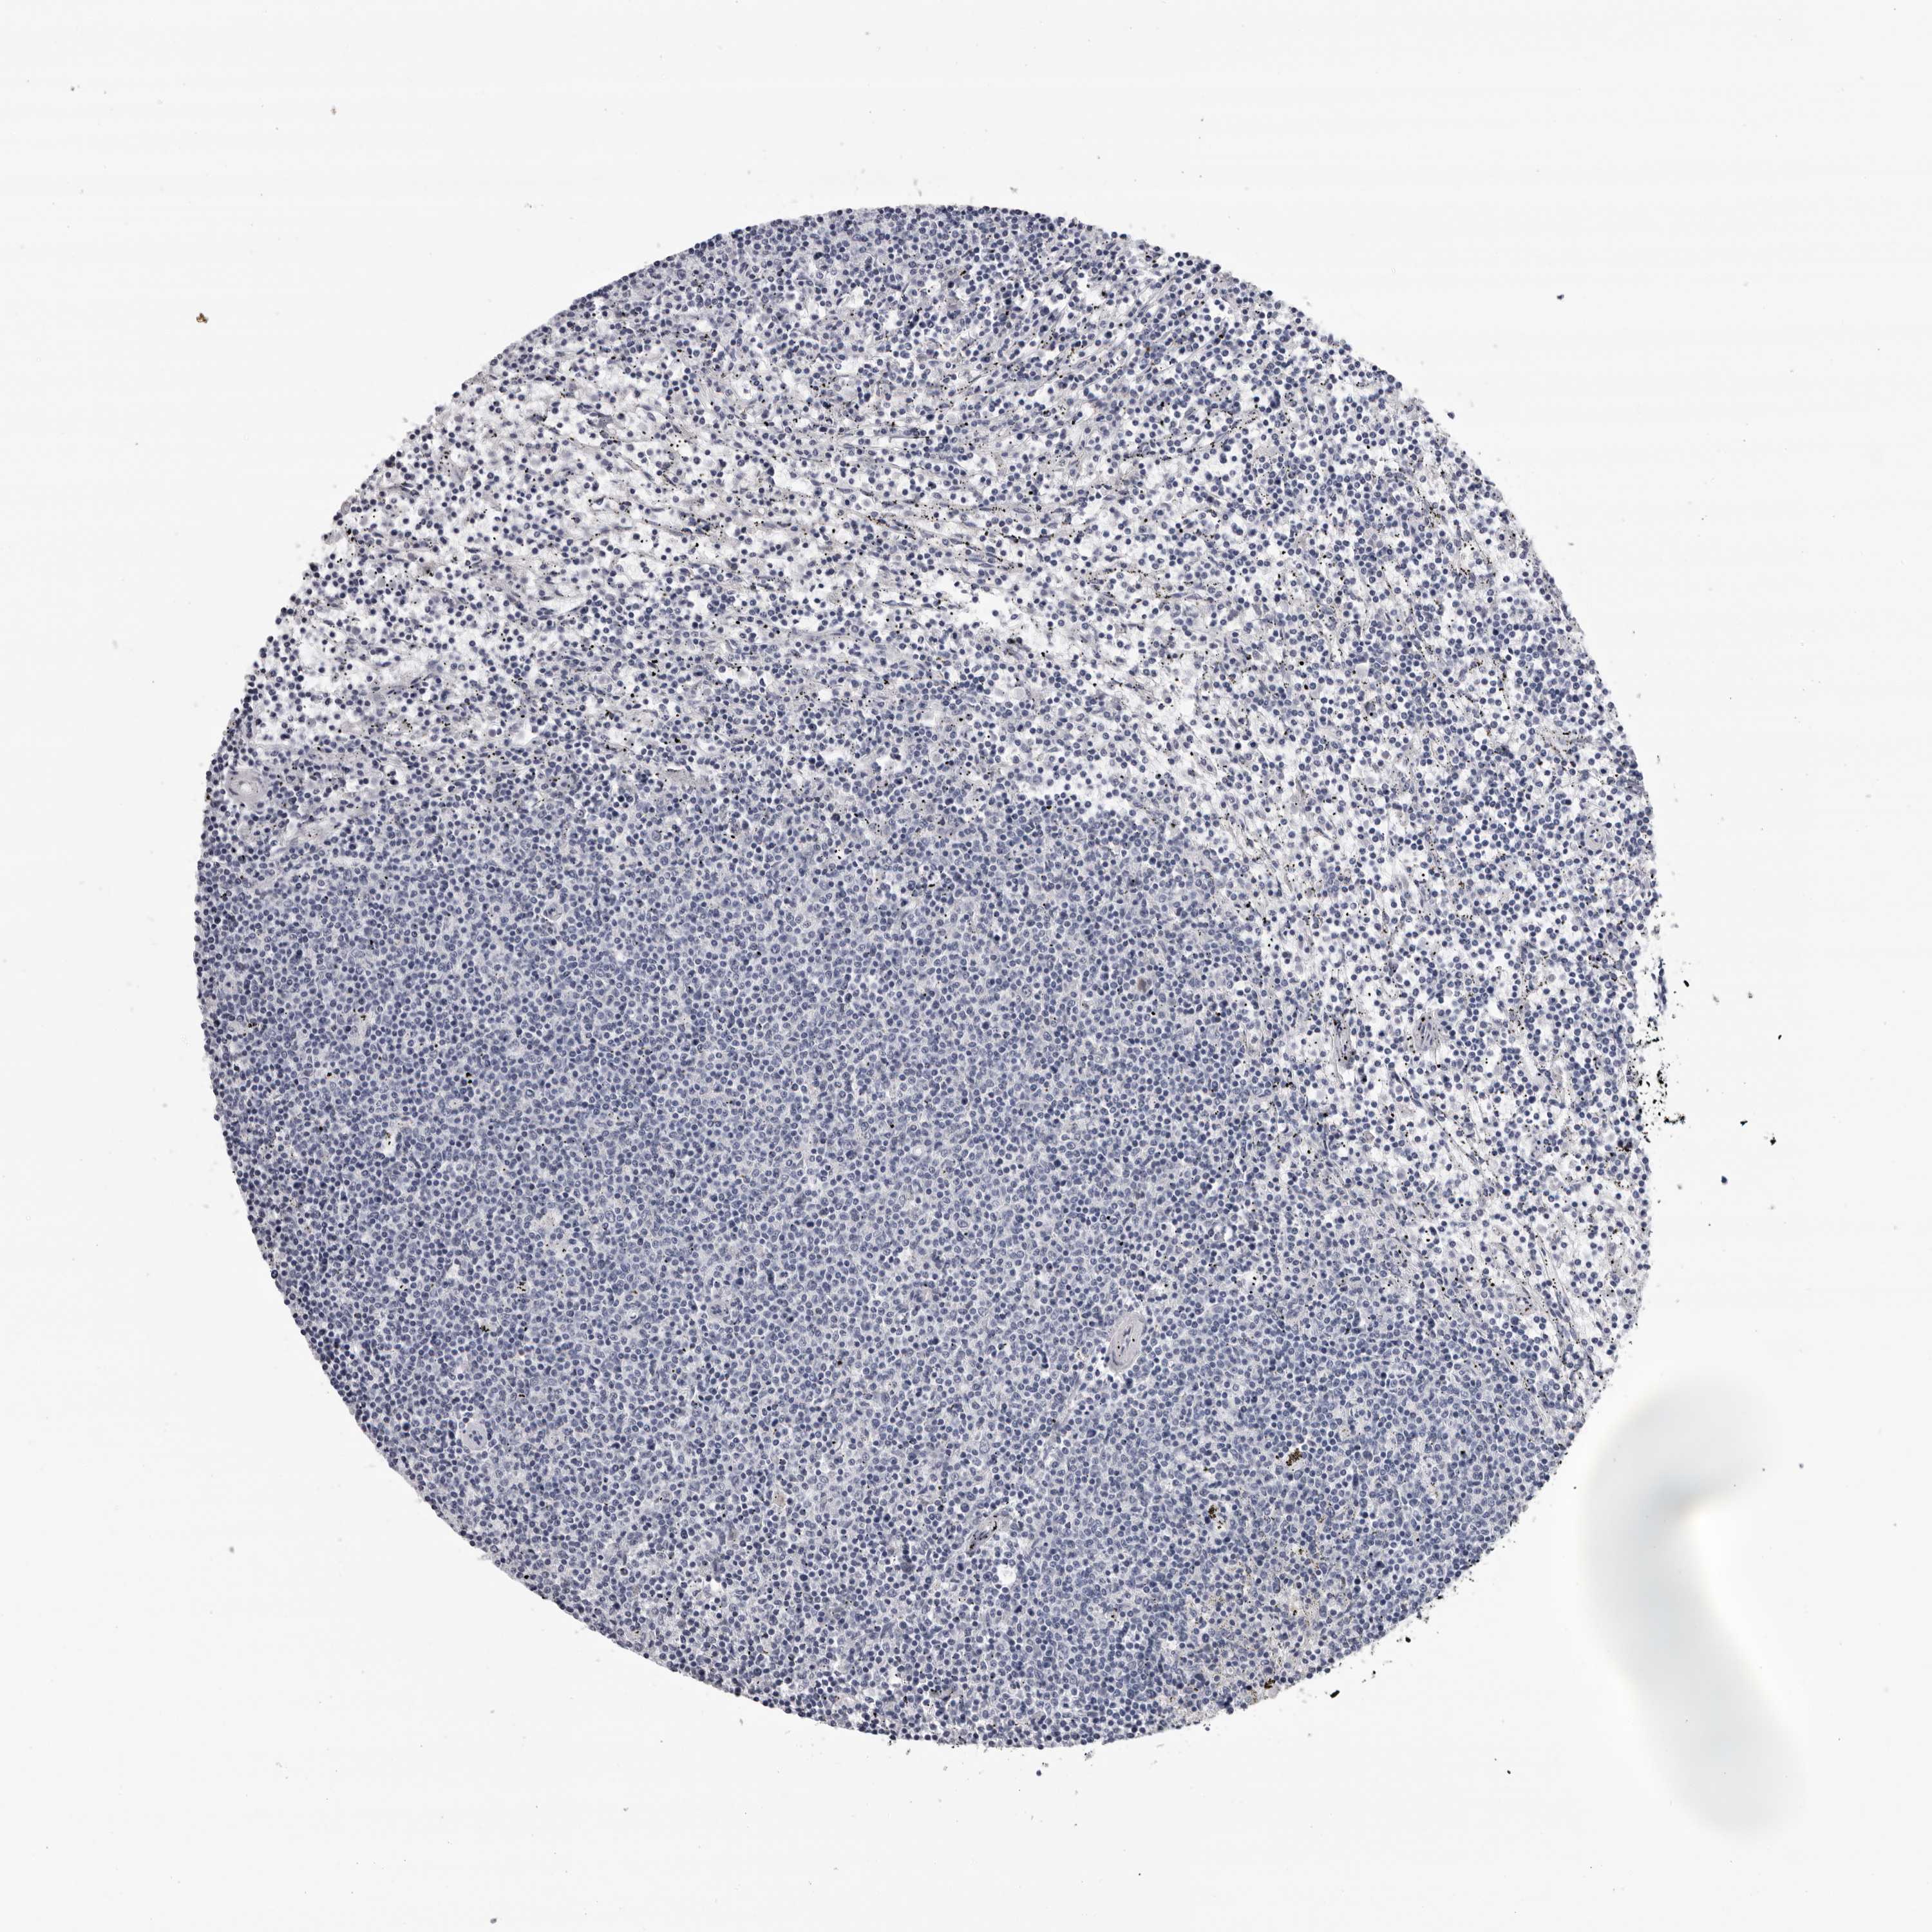

LYMPHOMA - Protein expressioni

A mouse-over function shows sample information and annotation data. Click on an image to view it in a full screen mode. Samples can be filtered based on level of antibody staining by selecting one or several of the following categories: high, medium, low and not detected. The assay and annotation is described here.

Antibody staining in the annotated cell types in the current human tissue is reported as not detected, low, medium, or high, based on conventional immunohistochemistry profiling in selected tissues. This score is based on the combination of the staining intensity and fraction of stained cells.

Each image is clickable and will lead to virtual microscopy that enables deeper exploration of all samples and also displays staining intensity scores, fraction scores and subcellular localization as well as patient and tissue information for each sample.

Antibody HPA024761

Hodgkin's disease, NOS

Malignant lymphoma, non-Hodgkin's type, High grade

Malignant lymphoma, non-Hodgkin's type, Low grade